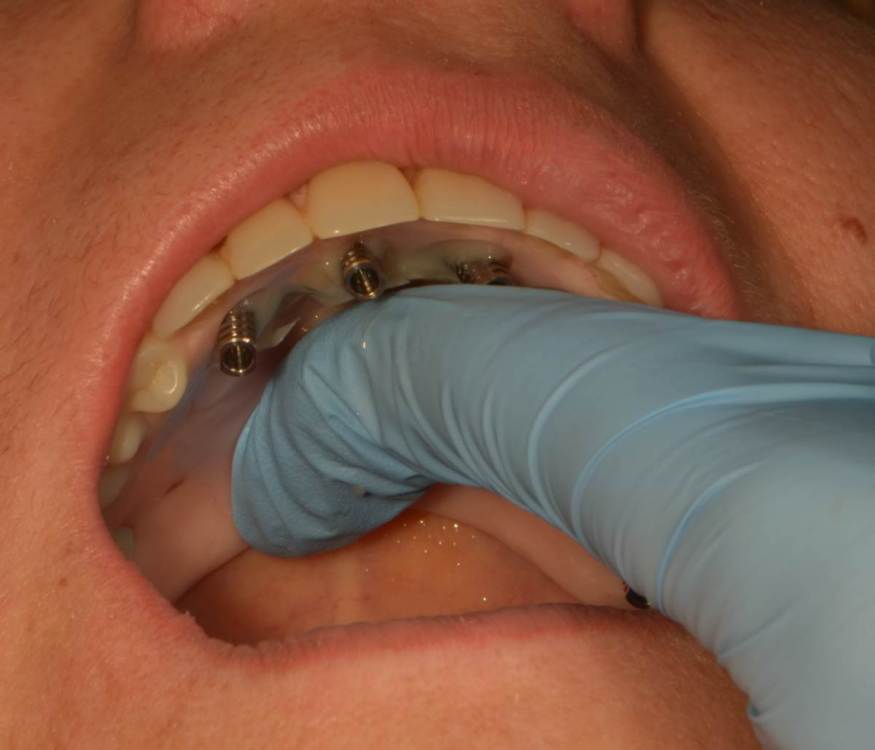

Мартовский Опубликовано 2 октября, 2023 Поделиться Опубликовано 2 октября, 2023 Там везде гной был или только в 14? Лучше зубы использовать для первого шаблона для правильной постановки пинов. А потом удалить и поставить второй шаблон, когда ложе под пины создано, тогда точно промашки не будет. 1 Ссылка на комментарий

Большой Зеленый Опубликовано 3 октября, 2023 Автор Поделиться Опубликовано 3 октября, 2023 Везде воспаление было. зубы оставшиеся точно не помощники были. Ссылка на комментарий